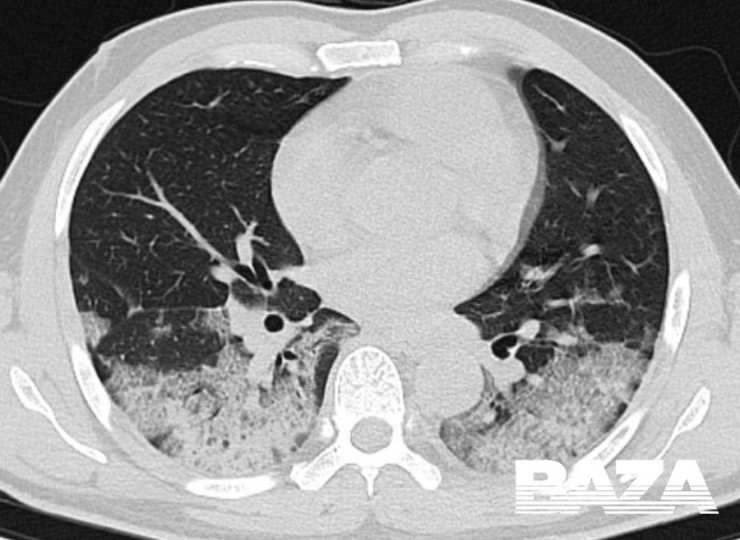

На пиковой стадии вирусной пневмонии (она развивается на 10–13-й день) появляются множественные уплотнения по типу "матового стекла" с различной протяженностью. Причем поражение может быть более обширным - субтотальным, с вовлечением всей доли целиком, а не только в пределах одного сегмента.